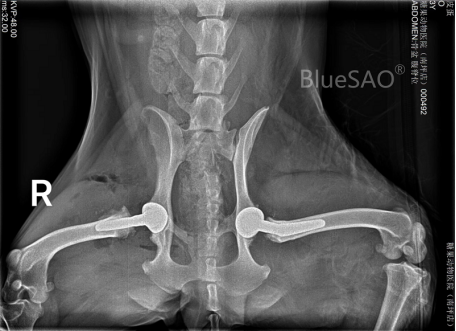

图 宠物髋关节